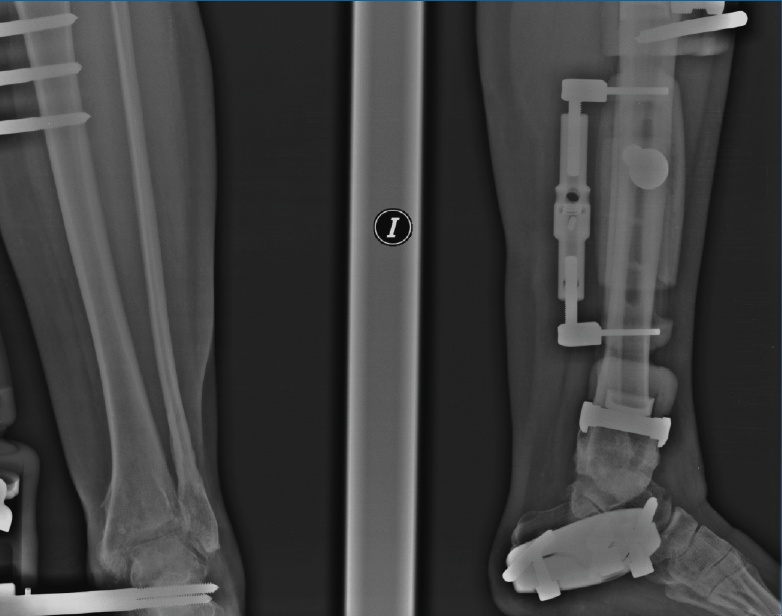

Figura 7. Caso de la Figura 6 con distracción articulada.

Figura 8. Caso de la Figura 6 a los 3 años de la distracción articulada. Obsérvese el mantenimiento del espacio articular a nivel de la articulación del tobillo.

Utilizamos el fijador articulado monolateral (de tipo X-Caliber®, Orthofix). En un primer paso procedemos a colocar los pines en astrágalo y calcáneo mediante la guía radiotransparente (Figura 2), para posteriormente colocar los pines tibiales en la superficie anteromedial de la misma (a ser posible 3). Al acabar el procedimiento procedemos a realizar progresivamente una distracción de entre 7 y 8 mm (se dispone de un calibrador en el fijador que nos permite visualizar la distracción que estamos realizando) (Figura 3) bajo control radioscópico, dejando finalmente la pieza articulada totalmente libre para la movilidad tibioastragalina desde el principio. Aplicamos un vendaje compresivo de la extremidad y retiramos la isquemia (Figuras 4 y 5).

El cuidado de los pines comienza el día siguiente de la cirugía hasta que estos estén secos. Los pacientes pueden asearse con precaución manteniendo bien secos los pines. La movilidad tibioastragalina es libre desde el principio y la fisioterapia comienza inmediatamente. Respecto a la carga, mantenemos una carga parcial de 20 kg con apoyo de muletas durante 10 días, para ir progresando según la tolerancia y la disminución del dolor hasta una carga completa, si bien el uso de muletas es aconsejable durante todo el tratamiento. Abogamos por mantener el fijador al menos 3 meses según propugnan van Valburg et al.(7,8) (los autores afirman que los condrocitos necesitan de 12 a 20 semanas de descarga para ser capaces de regenerar la matriz cartilaginosa); en caso de aflojamiento o intolerancia precoz de alguno de los pines, debemos adelantar la retirada del mismo (Figuras 6 a 8).